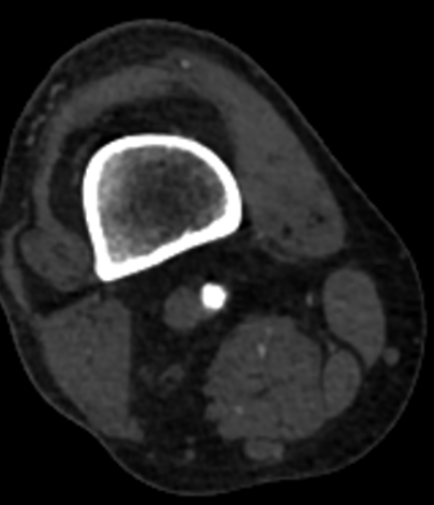

随后使用LiqMagic?P18外周血管内冲击波导管进行钙化斑块的压裂。根据血管尺寸,团队选择了4.0*60mm和5.0*60mm两个规格在4atm压力下逐段扩张整段病变,共进行了6个周期的冲击波治疗,将冲击波球囊加压至12atm显示病变狭窄解除,均匀扩开,保压1min后造影结果显示血流恢复通畅,钙化部位的残余狭窄明显改善。

▲5*60冲击波球囊扩张